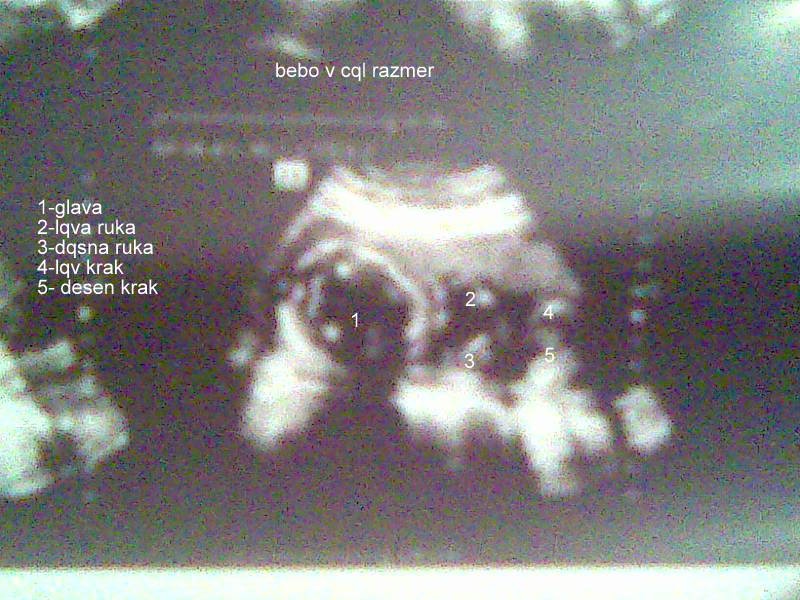

Ултразвук (11)

Ултразвук

Veche sme v 30+3...no sme baq golemki...i napuva da izliza ma ovladqvame polojenieto......a ti v koq si...tazi snimka ot mart

Zdr Mila v koq sedmica si?